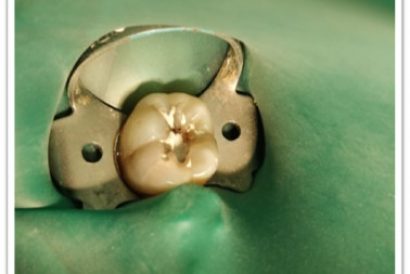

Patient Name:Chaitrali Patel

Tooth Involved :46

Diagnosis :Caries Involving Enamel And Dentin Approaching The Pulp : Sympotomatic Reversible Pulpitis

Treatment :Direct Pulp Capping With MTA

Restoration: Direct Composite Restoration Using Nanohybrid Composite

Before

After